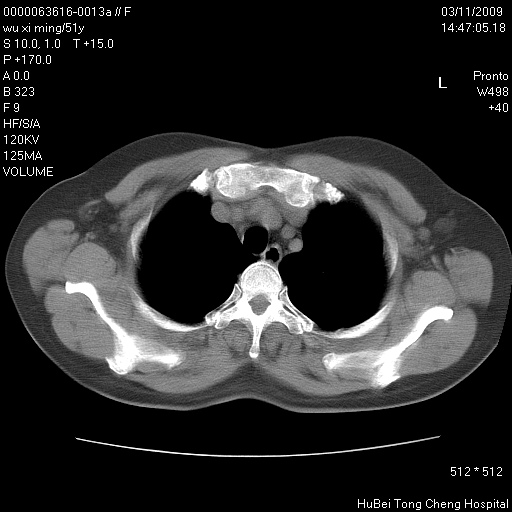

患者 女,51岁。因“胆囊炎,胆囊结石”,行常规术前胸部x线检查发现:右上肺结节病灶,建议行进一步检查。患者无咳嗽、咳痰及咯血等呼吸道症状,近期出现背部疼痛不适。

胸部ct轴位平扫(层厚10mm,螺距1.5,重建间隔10mm;部分层面:层厚3mm,螺距1.0,重建间隔3mm),图像如下:

右肺周围型肺癌伴肺内转移信胸椎转移

1、周围型肺癌。(毛刺正、血管束集征,分叶。)

集束征,胸膜牽拉征,毛刺,淺分葉高度提示ca.

右肺周围型肺癌伴肺内转移及胸椎转移。已无手术机会。